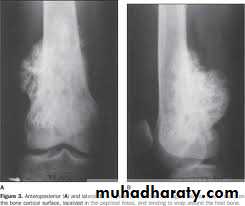

show a radiolucent area situated eccentrically at the end of a long bone and bounded by the sub- chondral bone plate.

The endosteal margin may be quite obvious, but in aggressive lesions it is ill-defined.

X-rays42

The Centre sometimes has a soap-bubble appearance.

The cortex is thin and sometimes ballooned. aggressive lesions extend into the soft tissue.43